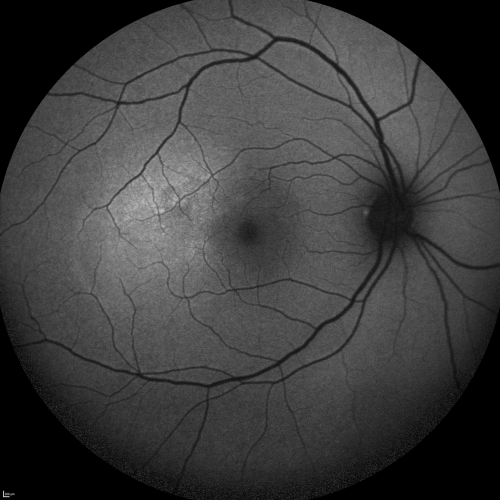

Central Serous Retinopathy Acute - Fundus Autofluorescence

42-year-old man was seen in the office on October 5, 2011.  He had noticed starting in August after a course of antibiotic and steroids, that he developed new spots in his vision in the right eye.  He may have had an episode like this sometime in the past.  He did take steroids a few years ago and his vision did change at that time, but then returned.

VISUAL ACUITY:  OD 20/32,  OS 20/32